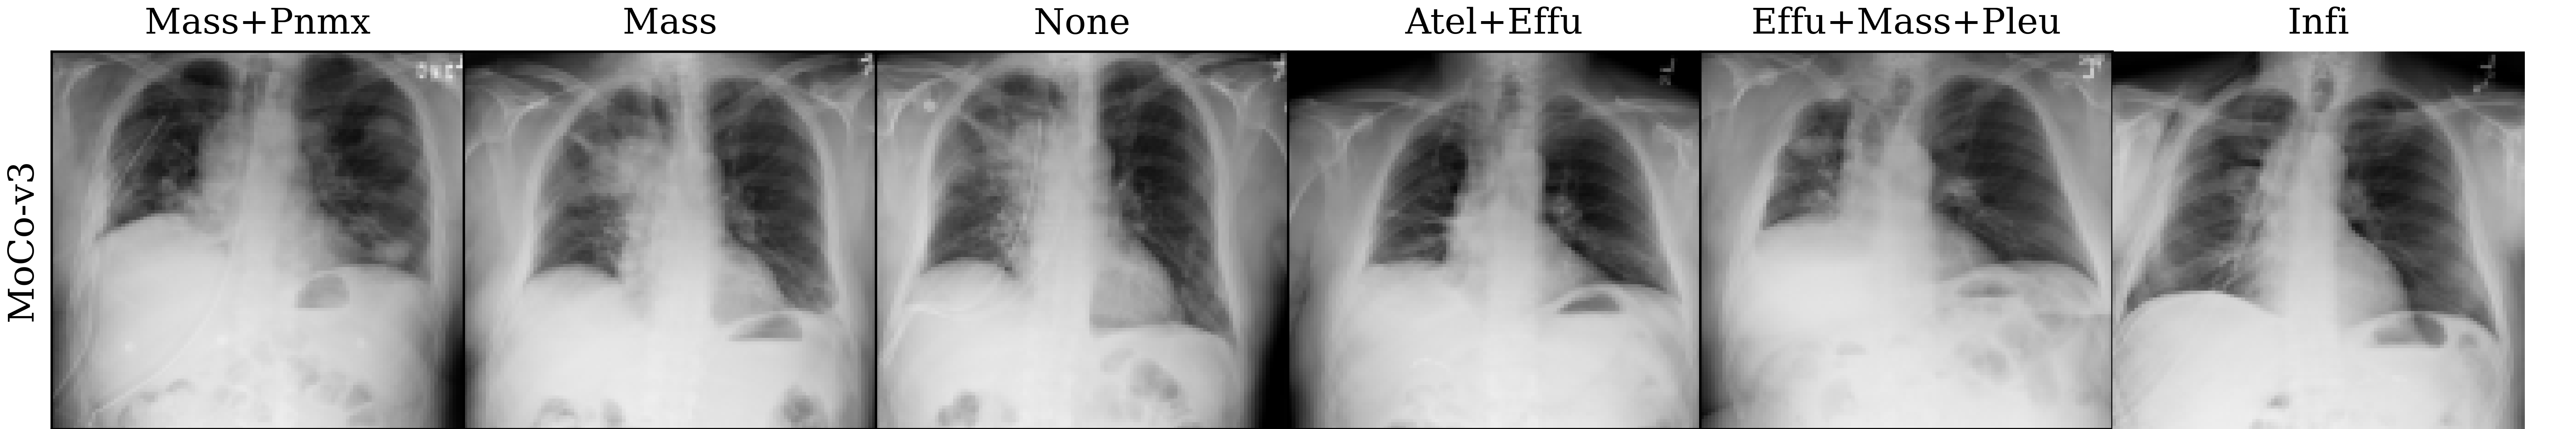

Lastly, we visualize the nearest neighbors in the embedding space of MoCo-v3 and MAE pre-trained models to yield insights into the pre-trained representations. To this end, we extract the last layer representations (after the layer norm) for both the train and test sets of ChestXray14. For each image in the test set, we compute the 5 nearest neighbors from the train set. The results are visualized in Figure 4, which reveals that the nearest neighbors of both MoCo-v3 and MAE largely preserve the overall shape of the query image. Additionally, we also perform a quantitative analysis by assigning the label of the nearest neighbor as the prediction for the query image. Under this nearest neighbor classification setting, MoCo-v3 has a slightly higher mAUC than MAE (52.7 vs 52.3), indicating that its pre-trained features are more linearly separable. This finding is in line with the observations made by He et al. (2022), who observed that the MoCo-v3 features are more linearly separable than MAE features. However, it is worth noting that despite MAE features being less linearly separable than MoCo-v3 features, the former captures more powerful non-linear features. This translates to stronger downstream models when the networks are fine-tuned instead of being used as fixed feature extractors, as evidenced by the superior fine-tuning results presented in Section 4.1.